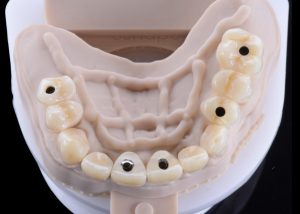

Second set of provisional restorations printed with GC Temp PRINT (medium shade) using the Asiga Max UV 3D printer. Fig. 13

Completed provisional crowns, implant retained crowns and bridge, characterized with OPTIGLAZE color (GC) – Dental technician: Brad Groblar, Oral Dynamics, New Zealand. Fig. 14

Completed provisionals fitted onto the printed models to allow the refinement of the contact points and occlusal contacts. Fig. 15 (i, ii)